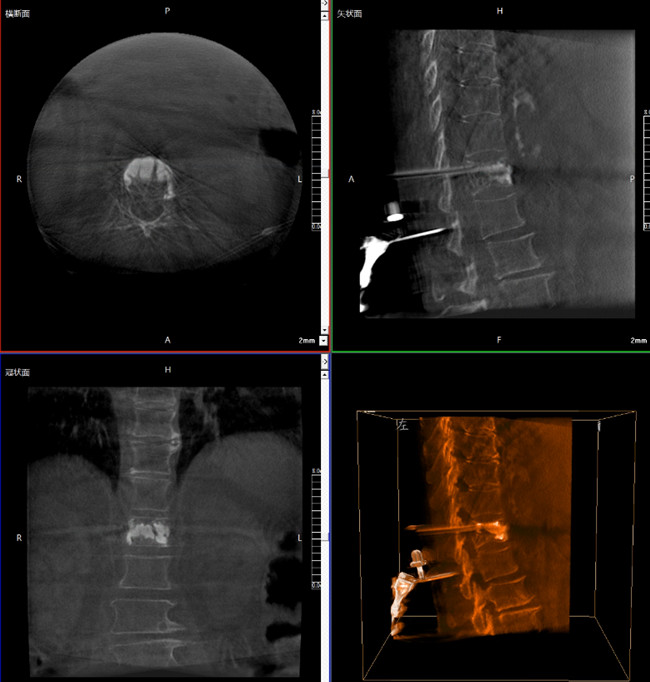

步驟一:C形臂三維重建+機(jī)器人手術(shù)規(guī)劃

使用普愛醫(yī)療三維C形臂對患者進(jìn)行胸椎影像掃描及三維重建,圖像被同步傳輸?shù)狡諓坩t(yī)療骨科機(jī)器人導(dǎo)航系統(tǒng)。

借助骨科機(jī)器人的規(guī)劃軟件進(jìn)行術(shù)前手術(shù)路徑模擬規(guī)劃,找到穿刺位置和角度,操作機(jī)械臂快速完成手術(shù)入點(diǎn)的準(zhǔn)確定位。

*術(shù)前規(guī)劃